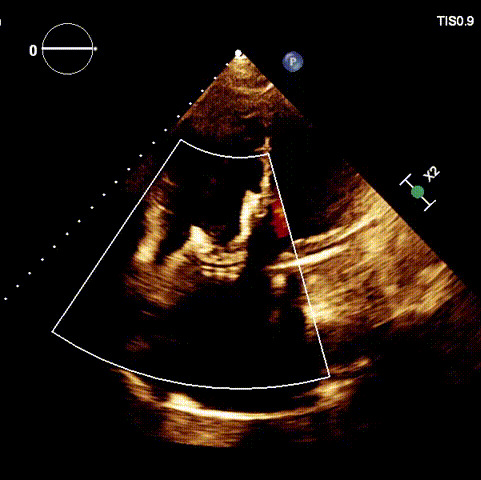

術后超聲

1.二尖瓣位機械瓣位置及功能未見異常;2.雙房及右室明顯擴大(左房收縮容積115ml,右房收縮容積370ml,右室中段左右徑65mm,右室FAC37%),下腔靜脈及冠狀靜脈竇擴張(下腔靜脈直徑44mm,冠狀靜脈竇直徑22mm);3.極重度三尖瓣反流(FTR 6+)。